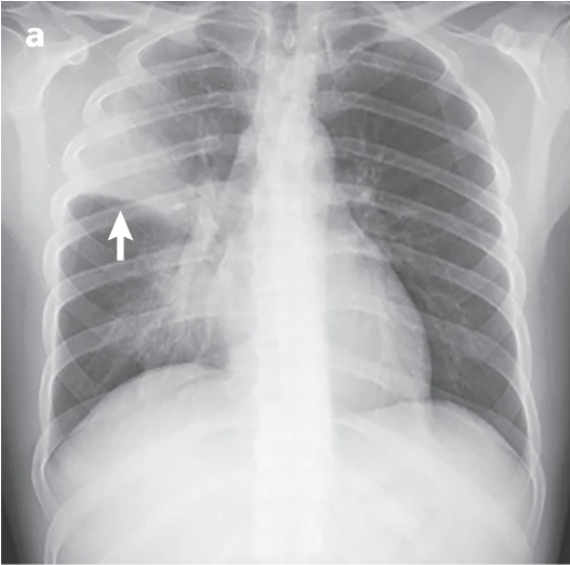

- Paciente de 40 años de edad, fumador desde los 18 años y sin antecedentes patológicos de interés. Consulta por cuadro de 24 horas de evolución de escalofríos, fiebre termometrada de 39 ºC, tos con expectoración y dolor pleurítico en el costado derecho. En la exploración física está consciente y orientado, la frecuencia respiratoria es de 34 rpm y la presión arterial sistólica de 115 mmHg. Se auscultan crepitantes en el campo medio y superior del hemitórax derecho. En la radiografía de tórax se observa una condensación en el lóbulo superior derecho (flecha).